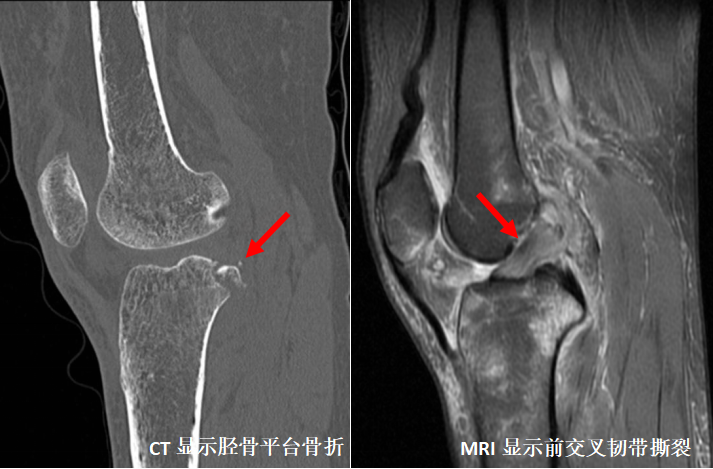

CT检查是多层断面成像,对于细微骨折、复杂部位骨折是强项

CT全称为计算机X线断层扫描,是一种常用的影像学检查方法。先由X线照射一定厚度的人体组织,然后通过接收器接收穿过该组织的X线,并将其转化为电信号和数字信号,最后通过计算机处理形成CT图像,具有较高的分辨率。CT检查可以从任意方向对图像进行二维重建和三维立体重建,避免骨头前后重叠造成的误解影像,并且能很好显示骨折线的走行、累及关节面情况,能够更好地评价骨折的严重程度。因此,对于某些特殊部位的细微骨折、需要进一步观察骨折线累及关节面情况、评估骨折严重程度的骨折,则需要进一步CT检查。

对于怀疑骨折后伴发有软组织、肌腱、韧带、软骨损伤的患者需要进一步MRI检查。